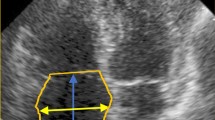

Clinical and biochemical assessments

Disease activity according to the DAS28 and the degree of disability by HAQ were evaluated19. A blood sample was collected after 10 h fasting to measure RF, anti-CCP, antinuclear anti-body (ANA), C-reactive protein (PCR), Erythrocyte sedimentation rate (ESR). Moreover, all patients were subjected to mono-dimensional (M-mode), bi-dimensional (B-mode), Doppler and color Doppler cardiac ultrasound (CUS) and via CUS probe 5-1 MHz. We evaluated: interventricular septum (IVSTd) and posterior wall thickness in diastole (LVPWTd), ventricular end-diastolic and end-systolic diameters (LVIDd, LVIDs) aortic root diameter, the end-diastolic diameter of the atrium. Relative Wall Tickness (RWT) was calculated according to the formula: (IVSTd + LVPWTd)/ LVIDd.